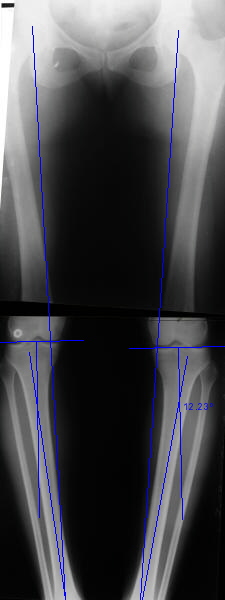

AC> Вот, с учетом и без учета, и на разных уровнях...

Из приведнной схемы не совсеим понял что означают разноцветные линии.

a> Из приведнной схемы не совсеим понял что означают разноцветные линии.

Черные - это нынешняя механическая ось. Красные - это планируемая правильная ось.